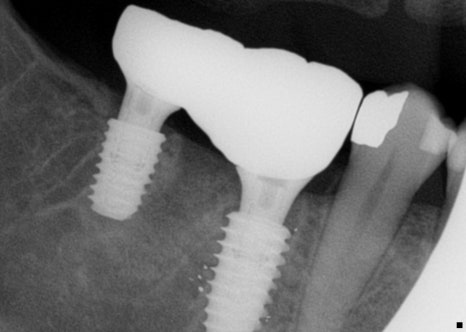

46번과 47번 치아에 어버트먼트를 장착한 후

스크류를 조이고 지르코니아 크라운을

장착하게 됩니다.

장착한 후에는 교합을 명확하게

확인할 필요가 있습니다.

치주인대를 한 번 더 확인하고

임시 접착 후 레진홀 충전을 진행합니다.